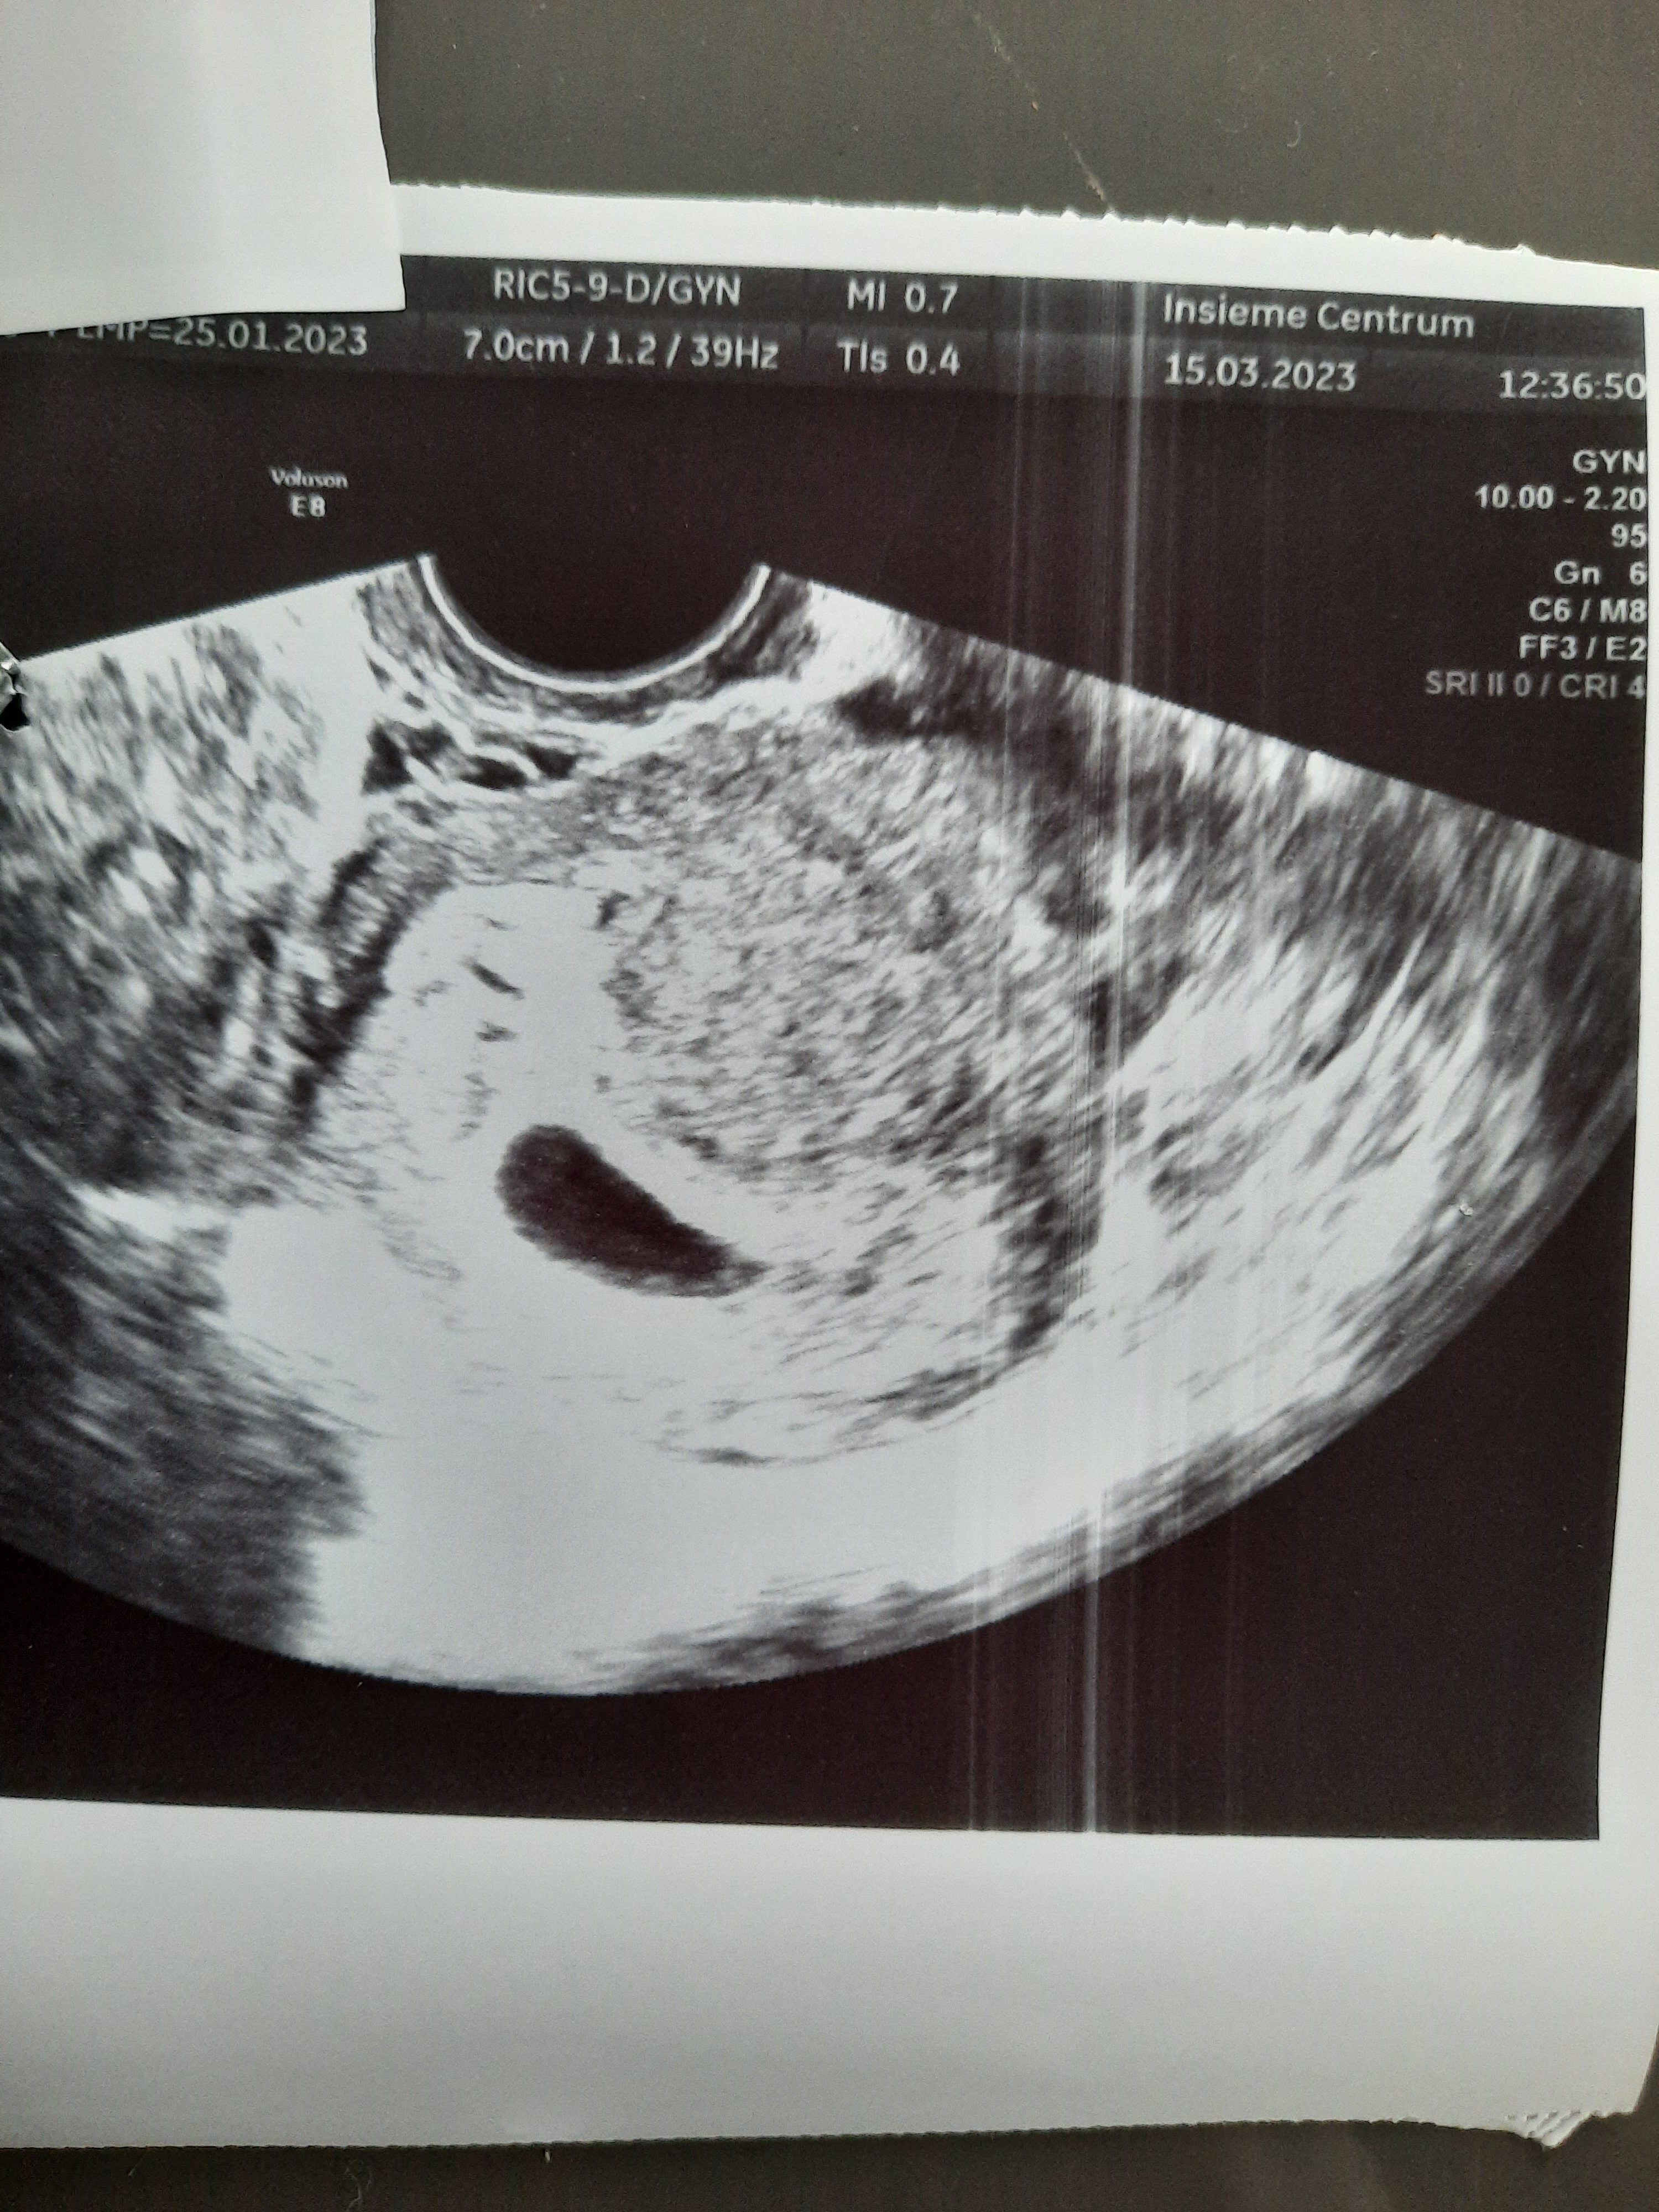

Od 6.03 biore 3x1duphaston. Byłam już u 2 lekarzy. Mam 2 zdjęcia z totalnie pustym pęcherzykiem. Dzisiaj jak pani doktor zaczęła bardzo kopać szukać to coś tam się jej pokazało i nazwała to "zatarte echo zarodka" które wyglada bardziej jak cień i sama nie była przekonana. Dla tego zleciła 2 bety.

Póki co prywatnie robiłam betę od razu jak test wyszedł pozytywny i wskazała 1326 a było to 3.03

A powiedziała jaka jest wielkość pęcherzyka ? Gdzies czytałam ( poprawcie jeśli się mylę) ze można z duża pewnością powiedzieć o pustym jaju gdy ten ma już 25mm.

Nic nie mówiła, ja w sumie nie wiedziałam że mogę o to zapytać. Może coś wynika z tego zdjęcia? Ale totalnie się na tym nie znam